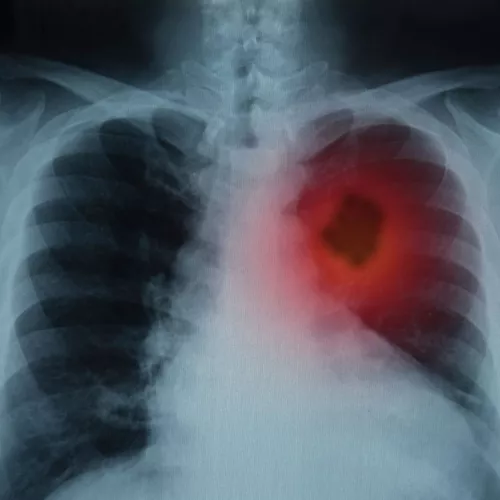

The ABCDEs of melanoma

Most moles are harmless. But ones that are new, changing, or unusual may spell trouble. Here’s what to look for.

- A is for asymmetry. The two halves don’t match.

- B is for border. The mole has an irregular border.

- C is for color. The spot has varying colors.

- D is for diameter. The mole is wider than a pencil eraser.

- E is for evolving. Any change in size, color, or shape could be a warning sign. Here, the bottom right section shows a melanoma growing from a mole (upper left section).